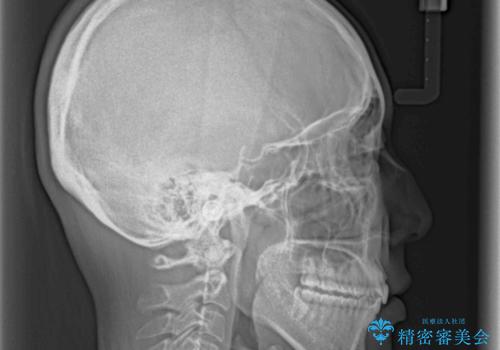

1日22時間の装着時間をしっかり守ってくださったので、予定通り1年で治療を終えることができました。

ディープバイトによる食いしばり癖も解消され、患者様には大変満足していただきました。